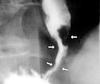

AXR: sentinel loop, pancreatic calcification

USS: gallstones and dilated ducts, inflammation